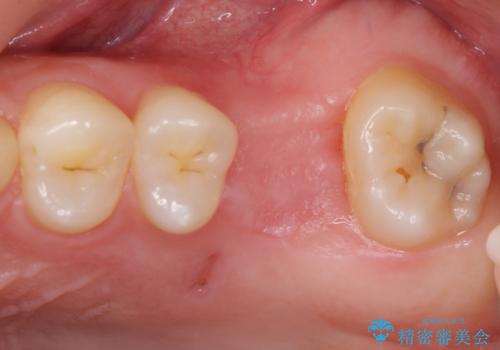

奥歯の虫歯は抜歯が必要であったので、矯正治療前に抜歯をし、矯正治療と並行してインプラントによる補綴治療を行うこととしました。